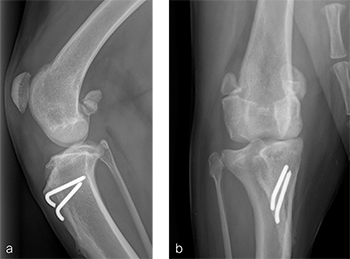

Case 2: Distal femoral osteotomy in a 1-year- and 6-month- old spayed female Appenzell Cattle Dog

A 1-year- and 6-month-old spayed female Appenzell Cattle Dog weighing 29 kg presented for second opinion after two previous surgical procedures to address a traumatically induced medial patellar luxation. Fig 8 illustrates the initial surgery performed at 1 year and 6 months of age. The patellar luxation was treated with a lateral imbrication. No primary orthopedic procedures were performed. X-rays were obtained 6 weeks postoperatively, and document persistence of the medial patellar luxation. Fig 9 addresses the revision surgery performed to address persistent patellar luxation. A tibial tuberosity transposition was performed to realign the insertion of the patellar tendon without addressing femoral deformity. X-rays were obtained 2 months postoperatively. The patellar luxation persists despite transposition of the tibial tuberosity. Orthopedic examination and preoperative x-rays revealed a grade 3/4 medial patellar luxation (Fig 9). Femoral varus was documented (aLDFA 104; normal 9296) by CT scan (Fig 10). The planned correction was a 10 lateral closing wedge ostectomy, with concurrent sulcoplasty.